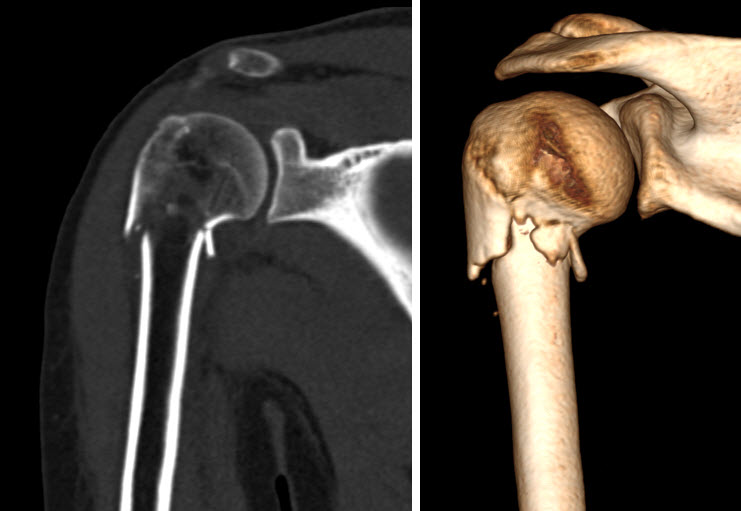

În cazul unui afecțiuni traumatice, cu leziune aparentă sau nu pe radiografie, se preferă uneori computer tomografia, mai ales dacă ortopedul are nevoie de reconstrucția 3D a osului. Având în vedere că CT-ul nu poate vizualiza corespunzător structurile labrale, ligamentare și tendinoase și nici cartilajul, rezonanța magnetică este cea indicată în cele mai multe cazuri.

Examinarea prin computer tomograf a umărului

Examinarea prin computer tomograf a umărului se indică în traumatismul cu suspiciune de fractură, dizlocații gleno-humerale, tumori, alte patologii atunci când examinarea prin rezonanță magnetică nu este disponibilă sau este contraindicată.

Examinarea prin computer tomograf durează câteva zeci de secunde, în funcție de rapiditatea computer tomografului și poziția pacientului este similară cu cea de la examinarea prin rezonanță magnetică. Uneori, în cazuri dubitabile, este nevoie să scanăm umărul bilateral, spre exemplu pentru a elucida prezența unei eventuale variante anatomice.

Achiziția imaginilor se face după protocoale dedicate articulațiilor mari, în care avem nevoie de o scanare fină, eventual cu ținerea respirației pentru a evita artefactele de mișcare. Scanarea trebuie să se limiteze la zona de interes pentru a nu iradia inutil pacientul, dar fără să scăpăm din vedere faptul că fracturile, mai ales cele spiroide pot fi foarte lungi și trebuie să avem în imagine tot traiectul.

După achiziția inițială a imaginilor, pacientul poate să părăsească computer tomograful, urmând partea mai complicată de postprocesare, în care este nevoie de reformatări în toate planurile, atât coronal, cât și sagital și de analiza imaginilor atât în fereastra dedicată de os, cât și în fereastra dedicată țesutului moale. Se realizează reconstrucții 3D ale regiunii scanate, pentru o mai bună exemplificare a regiunii. Aceste proceduri postprocesare sunt deosebit de laborioase și de obicei sunt realizate de către medicul radiolog sau de un operator foarte bine pregătit.